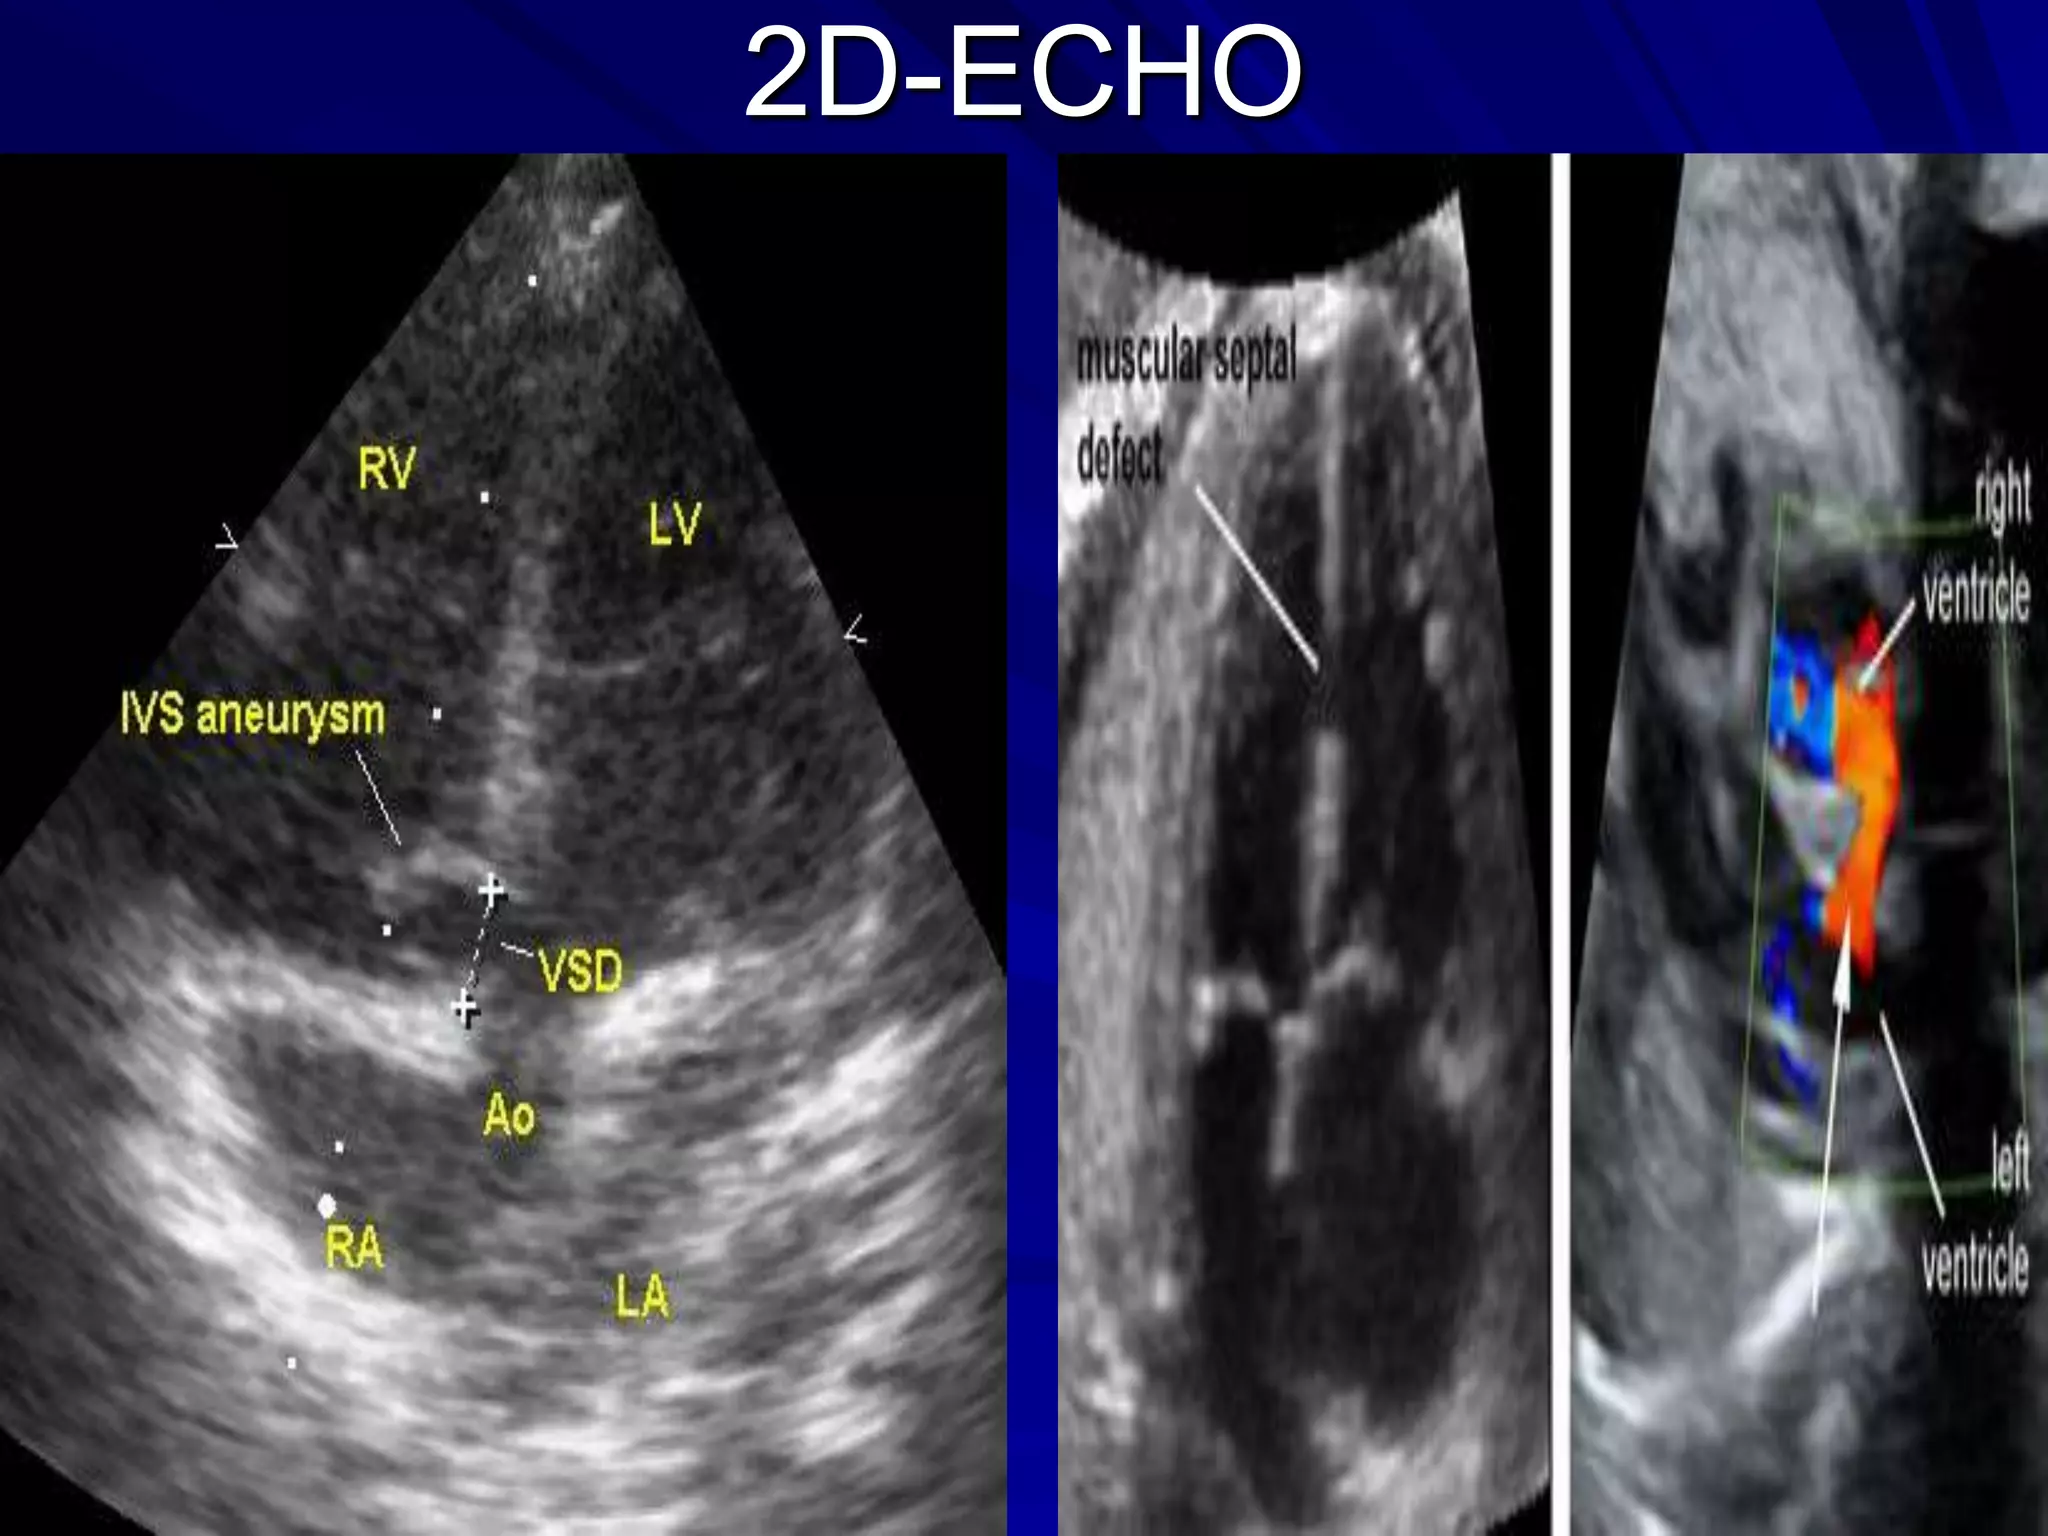

2D -ECHO

Determine vsd location

LV outflow morphology

Aortic valve

involvement

AV valve chordal attachment

Septal trabeculations

may cause multiple

reflections and obscure

small defects

Prominent bulging of

tissue into the RV :

aneurysmal

perimembranous VSD

2D-ECHO

Supracristal VSD, with pulm outflow tract obstruction